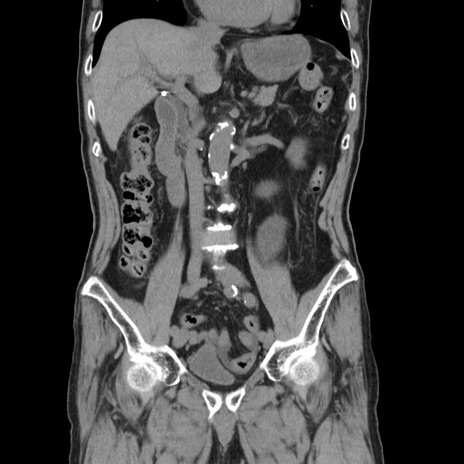

症例24(冠状断像)

【症例】80歳代男性

【主訴】左側腹部痛、嘔吐

【現病歴】本日早朝より左腹部に痛みあり。昼頃嘔吐認めたため、救急要請。

【既往歴】直腸癌(Mile手術)、胆摘

【身体所見】意識清明、BT 35.9℃、BP 221/93mmHg、SpO2 97%(RA) 、腹部:左ストーマ周囲に限局性の腹部膨隆あり。 膨隆部自発痛・圧痛あり・軟。

【データ】WBC 7700、CRP 0.09